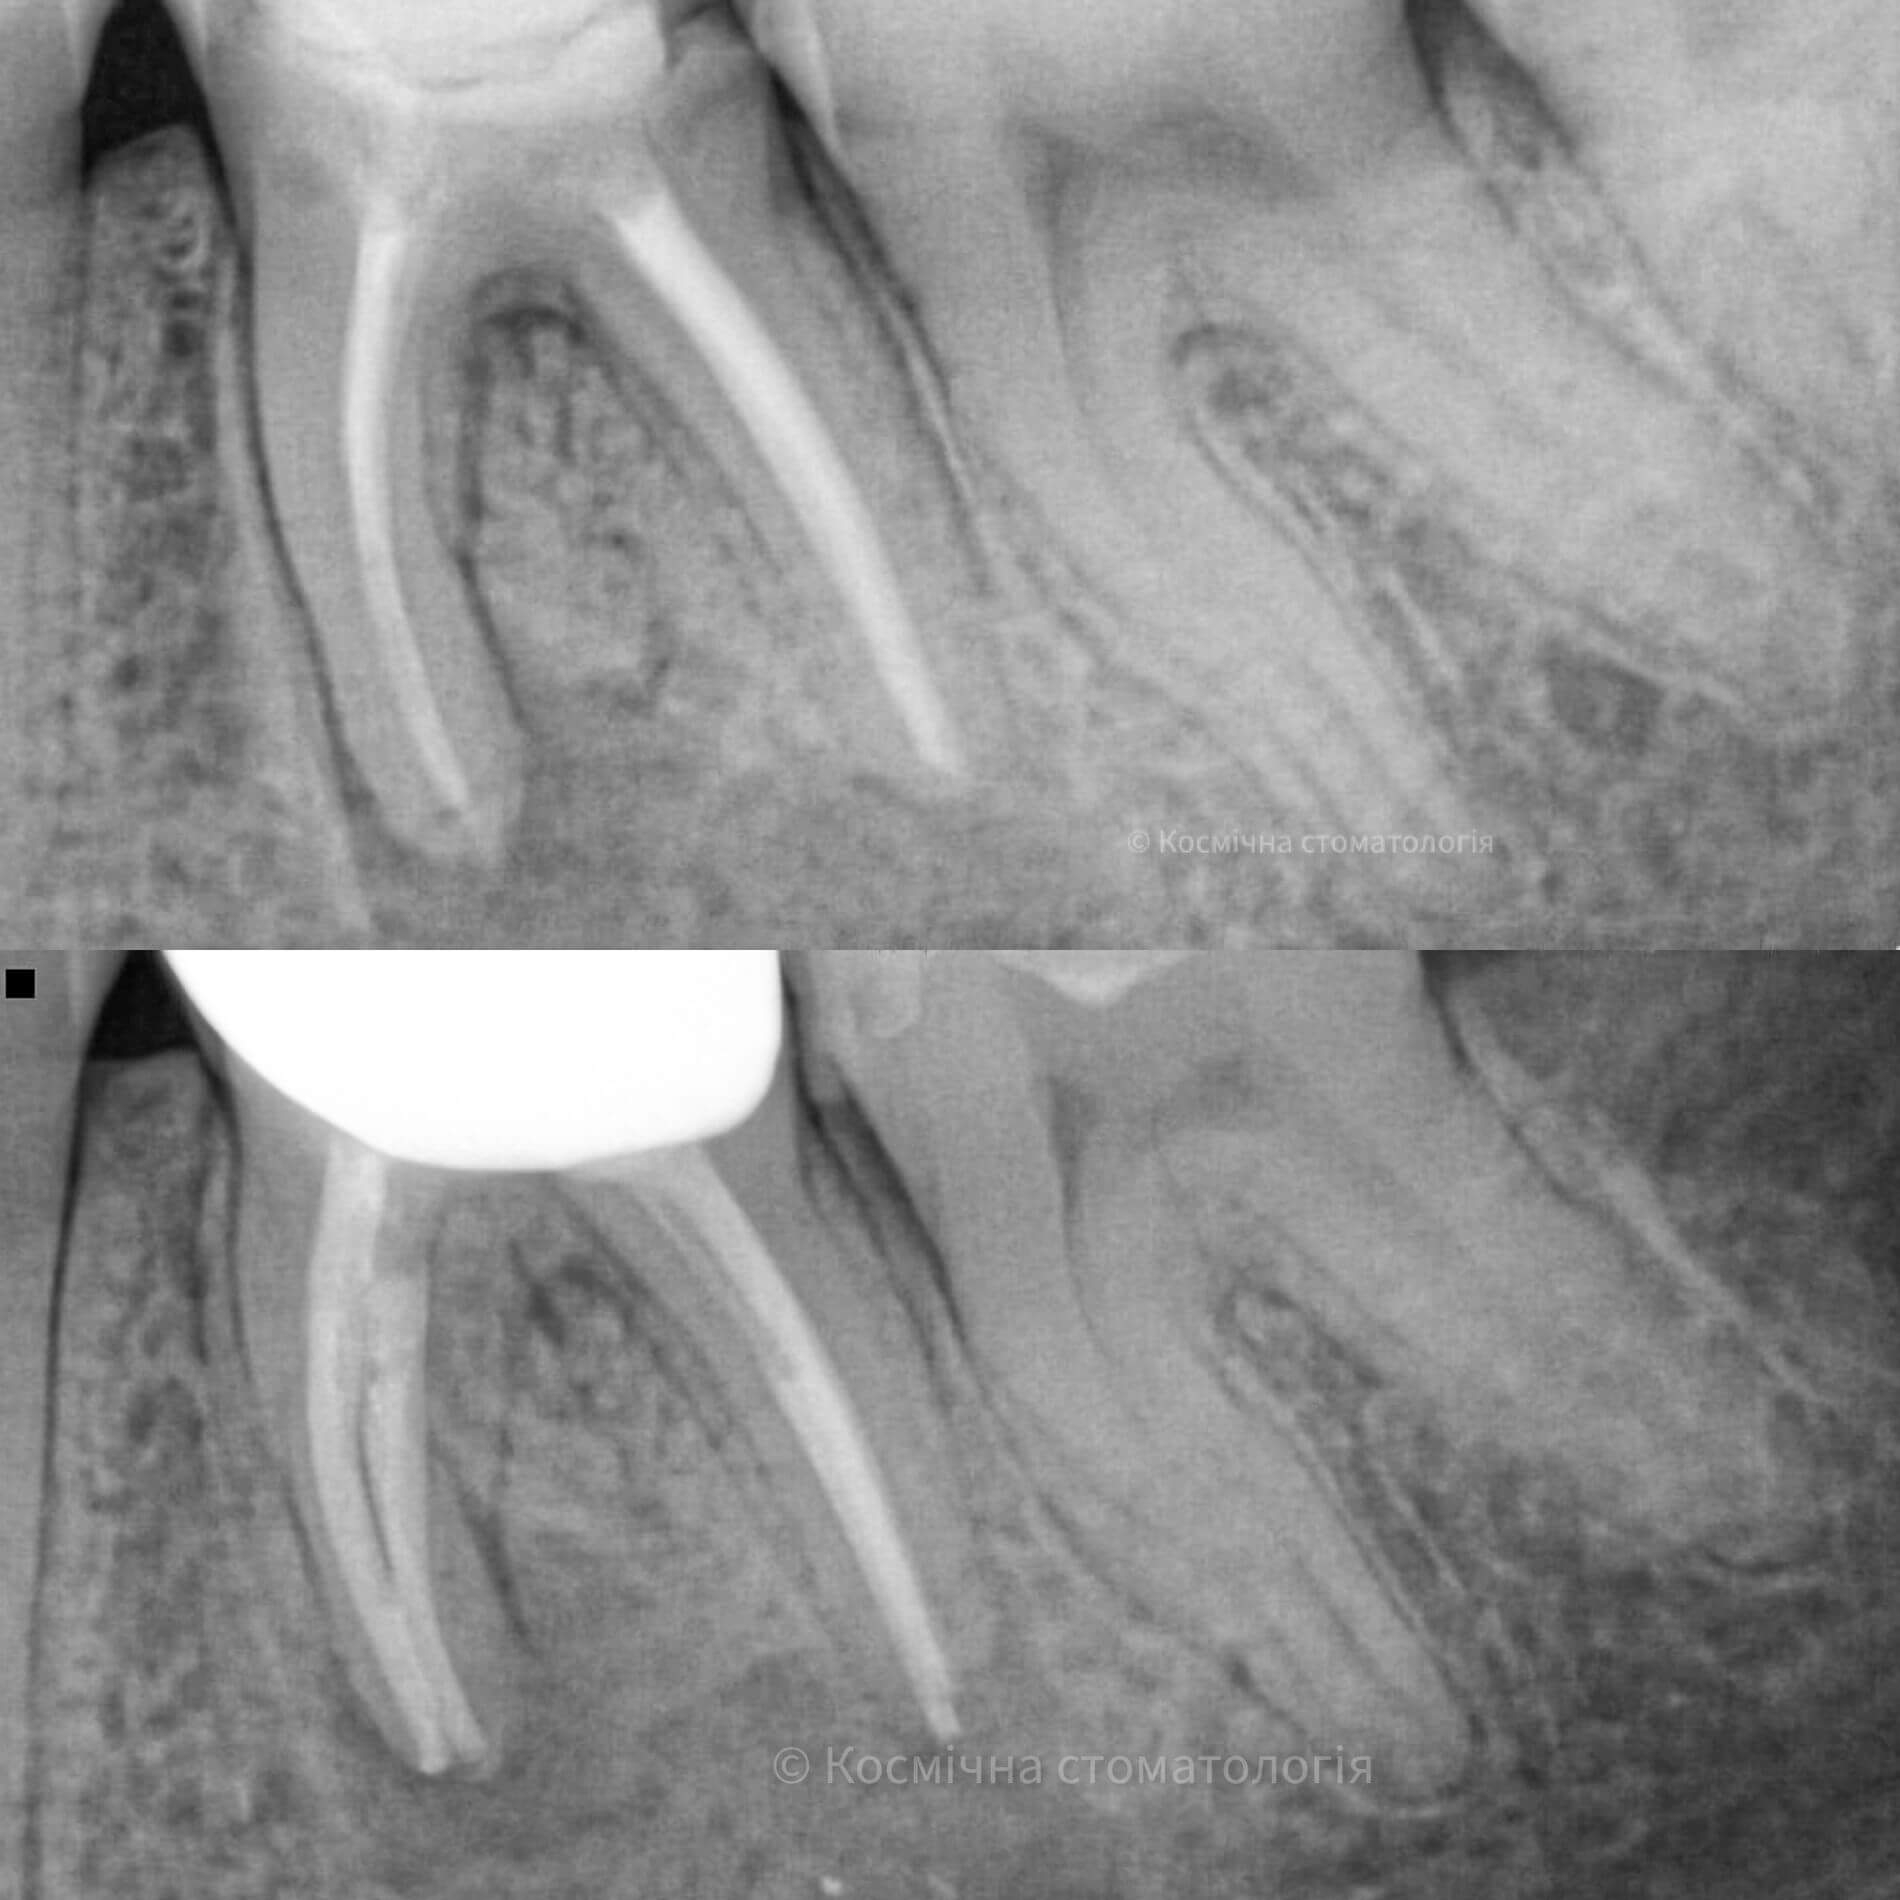

- 3D пломбирование корневых каналов горячей гуттаперчей. Высокоэффективная техника, позволяющая заполнить все ответвления корневых каналов настолько плотно, чтобы достичь абсолютной герметизации. А значит, ни одна инфекция не сможет повторно поразить корневые каналы твоего зуба.

- Пломбирование зубных каналов биокерамикой. Крутая и инновационная технология, набирающая популярность в эндодонтии. Соединила в себе три качества: биоинертность, биоактивность, биосовместимость.

Иногда случаются ситуации, когда даже после лечения и удаления инфицированного содержимого зубного корня зуб продолжает болеть. Мы надеемся, тебе не пришлось с таким сталкиваться, но помни это тревожный сигнал, что лечение каналов было проведено ненадлежащим образом: инфицированная пульпа не была удалена до конца, плохо проведена дезинфекция или негерметичное пломбирование. Такие недостатки в лечении приводят к повторному инфицированию, возникновению воспалительного процесса с последующей потерей зуба.